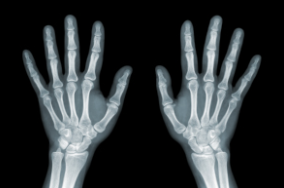

1️⃣ X-ray 성장판 촬영

가장 기본적인 검사입니다.

- 왼손과 손목 부위 X-ray를 통해 뼈의 성장 상태를 파악

- 성장판이 열려 있는지 닫혔는지 확인 가능

2️⃣ 골연령(뼈 나이) 측정

- 실제 나이와 골연령을 비교해 성장 가능성을 예측해요.

성장판 검사(주로 손목 X-ray를 통한 골연령 측정)는 아이의 성장 잠재력을 예측하는 데 유용하지만,